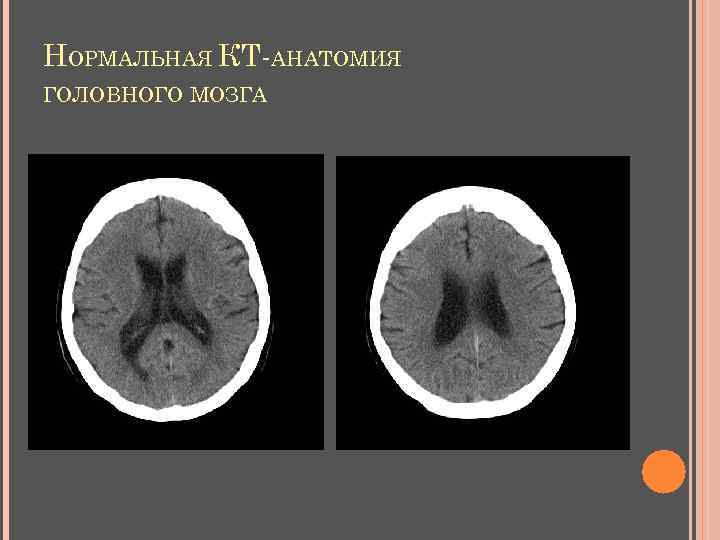

НОРМАЛЬНАЯ КТ-АНАТОМИЯ ГОЛОВНОГО МОЗГА Неизмененные ткани мозга: серое вещество 36 -40 ед. НU, белое вещество 24 -36 ед. НU